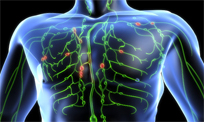

MLD can lessen the swelling resulting from the body's inflammatory responses to soft tissue traumas that may be caused by...

CDT is a combination of the Dr. Vodder method of Manual Lymph Drainage, remedial exercise therapy, compression bandaging...